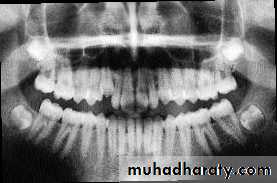

Position of canine root apex anteroposteriorly

Vertical canine crown height